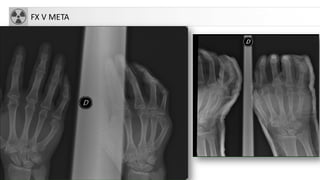

FRACTURASMETACARPIANOS

• 30-50% de fracturas de la mano

• Mecanismo: trauma directo

• Más frecuente:FX cuello de V meta: “FX del boxeador”

FX V META